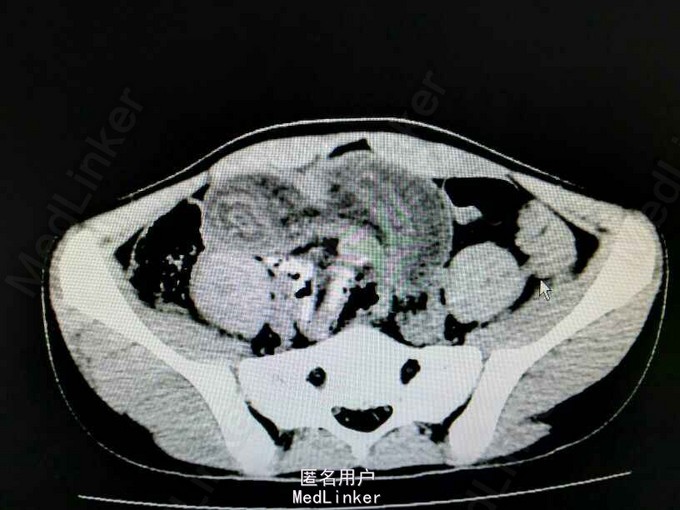

患儿,男,13岁,因“黑便伴右下腹痛7 小时”入院。 患者7小时前无明显诱因出现腹痛,位于右下腹,为持续性绞痛,休息可缓解,疼痛无放射 至其它部位,伴有恶心、呕吐,无伴发热、返酸、嫒气、腹胀、腹泻、呕血、黑便、血便, 遂到我院急诊就诊,行腹部CT 提示”考虑肠套叠,局部肠管水肿”,为进一步诊治,急诊 拟“腹痛查因:肠套叠”收入我科。

腹平,腹软,脐周及右下腹压痛,反跳痛可疑,腹部移动性浊音(-),肠鸣音4次份。 腹部ct提示“下腹部局部小肠肠壁明显增厚,密度减低,局部可见肠管套入,可见多层肠壁显示。考虑肠套叠,局部肠管水肿”。